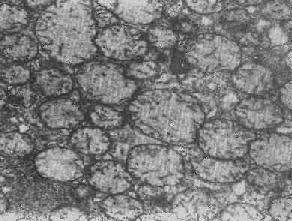

1.初级溶酶体为除水解酶类外不含其他物质并尚未参与细胞内消化过程的溶酶体,例如中性粒细胞中的嗜天青颗粒、嗜酸性细胞中的颗粒以及巨噬细胞和一些其他细胞中的高尔基小泡(图1-13)。

图1-13 初级溶酶体

图中央及中下方之卵圆形电子致密小体,外围单层包膜。(图中及下部片层状膜性结构为粗面内质网(正常肝细胞)×12000

2.次级溶酶体为除溶酶体的水解酶外尚含有其他外源性或内源性物质并已参与细胞内消化过程的溶酶体(图1-14),亦即含有溶酶体酶的各种噬体,因而称为吞噬溶酶体(phagolysosome),乃由吞噬体与初级或次级溶酶体融合而成。

图1-14 肝细胞内次级溶酶体 ×28000